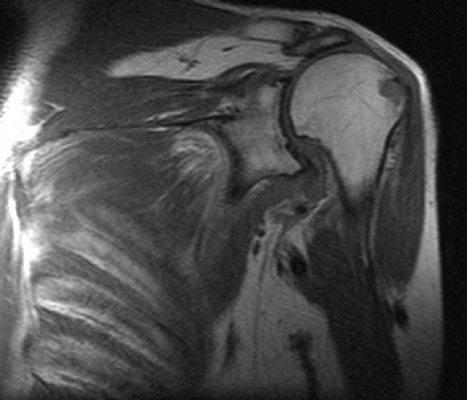

Плоскость сканирования: аксиальная, корональная, сагиттальная

Вид исследования: левый плечевой сустав

На серии МР томограмм взвешенных по Т1 и Т2 в трех проекциях получено изображение плечевого сустава. Контуры суставных поверхностей ровные, чёткие, не деформированы краевыми костными разрастаниями. Суставная щель не сужена, признаков подвывиха головки плечевой кости не выявлено. Мелкие кисты до 2-Змм в головке плечевой кости.

Фиброзно-хрящевая губа гленоида обычно расположена, форма её не изменена, целостность не нарушена.

Количество жидкости в полости плечевого сустава физиологическое. Небольшое количество жидкости в подклювовидной сумке. Определяется незначительное количество жидкости по ходу сухожилия длинной головки бицепса.

Субакромиальное расстояние - 6,5мм. Жидкости в подакромиальной сумке не определяется.

Дельтовидная мышца без особенностей.

Акромиально-ключичное сочленение - смежные поверхности акромиона и ключицы не деформированы.

Суставная ямка лопатки с ровными чёткими контрами, краевыми костными разрастаниями не деформирована. Гиалиновый хрящ не истончен.

Подклювовидный бурсит, незначительное количество жидкости по ходу сухожилия длинной головки бицепса.